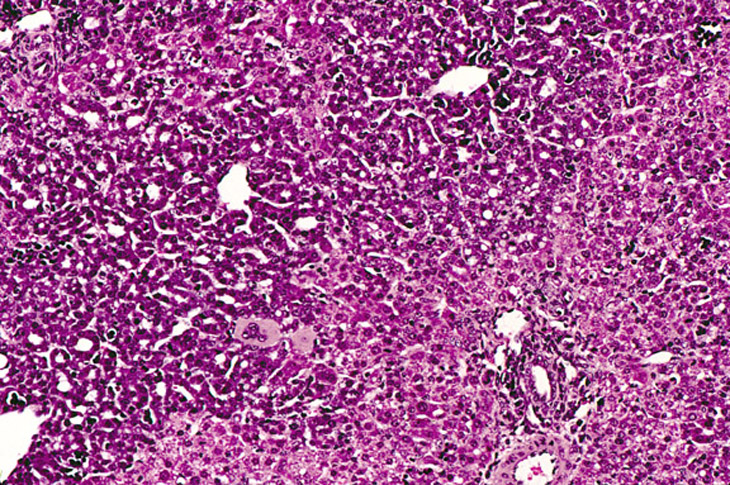

Hepatocellular adenoma and bile duct carcinoma in a 4-week-old transgenic mouse.

A proliferative cystic biliary lesion, a solid basophilic adenoma, and a bile duct adenoma in a 4-week-old transgenic mouse.